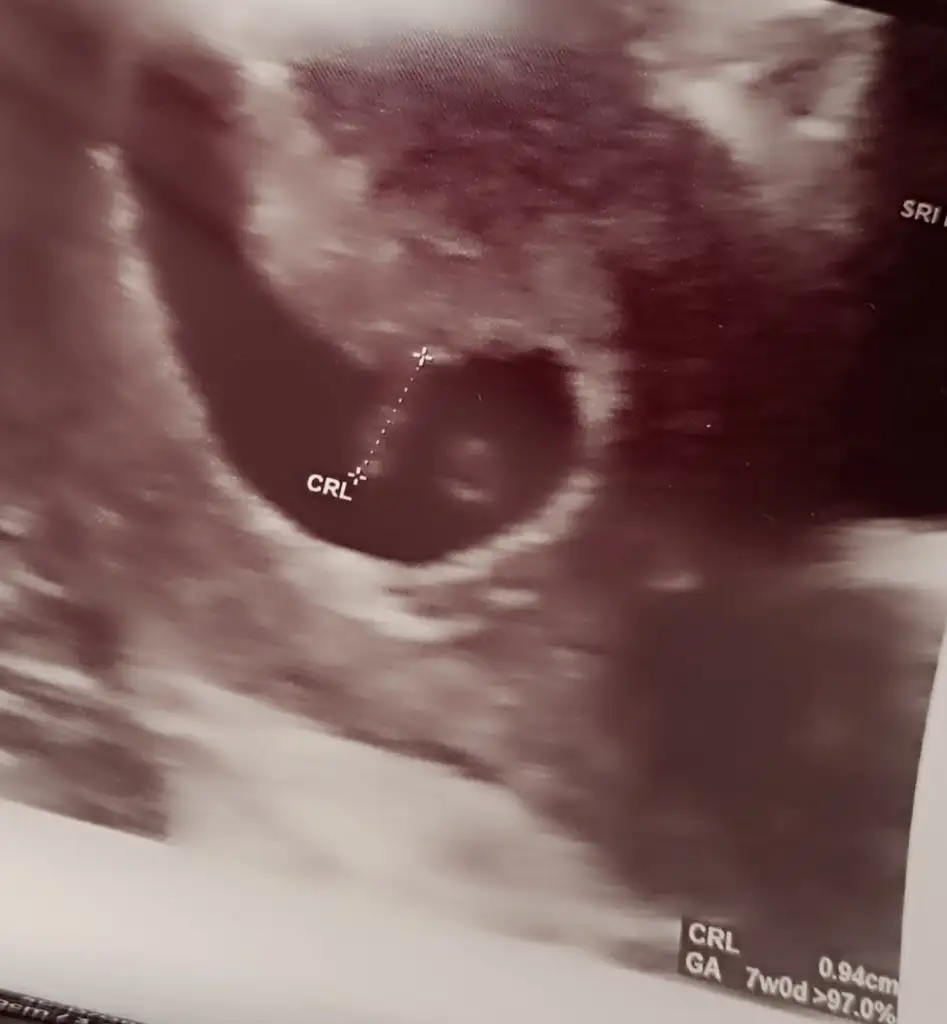

Doktor kesenin boyunu ölçmemiş ölçseydi çıkardı. Haliyle daha bebekte görünmediği için onunda haftası yazılı değil bi dahaki kontrolünüzde çıkar haftası. Ben normalde doktora gittiğimde geçen hafta 6+6ydım ama bebeği ölçtü 7+2 çıktı. Bebek görünsün sizinde haftanız gününüz görünürEki Görüntüle 3210472

Çok teşekkür ederim bilgiler içinDoktor kesenin boyunu ölçmemiş ölçseydi çıkardı. Haliyle daha bebekte görünmediği için onunda haftası yazılı değil bi dahaki kontrolünüzde çıkar haftası. Ben normalde doktora gittiğimde geçen hafta 6+6ydım ama bebeği ölçtü 7+2 çıktı. Bebek görünsün sizinde haftanız gününüz görünür

Sizin dediğim gibi ölçmemiş bebek boyunu sağdakiler nedir anlamadım genel bilgi falan olabilir. Bir dahaki sefere kalmış, olsun sağlıkla büyüsün de. Benim dediğim bu şekildeydi.Eki Görüntüle 3210472

Hmmm anladım teşekkür ederim. 2 martta kontrol var umarım o zaman ki ultrason da yazar. Doktor zaten bu sefer net bilgi verir diye düşünüyorum. Yani inşallahSizin dediğim gibi ölçmemiş bebek boyunu sağdakiler nedir anlamadım genel bilgi falan olabilir. Bir dahaki sefere kalmış, olsun sağlıkla büyüsün de. Benim dediğim bu şekildeydi.